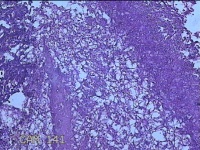

右侧窦腔内容物

性别

男

年龄

49岁

临床诊断

1.慢性鼻窦炎 2.鼻中隔偏曲 3.变应性鼻炎

一般病史

鼻塞、脓涕2月,加重伴涕中带血1周。

标本名称

大体所见

灰白暗红色不规则碎组织1.5x1.3x0.3cm一堆。

图3